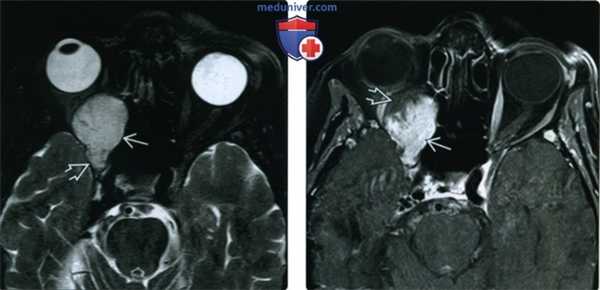

(Справа) При Т1-взвешенной МРТ в аксиальной проекции определяется инфильтративное образование, распространяющееся на несколько смежных пространств. В задней части образования, лежащей в пределах мышечного конуса, в просвете макрокистозных полостей видны уровни жидкость-жидкость. Пресептальный и передний внутриглазничный компоненты выглядят более гомогенными и гипоинтенсивными, что указывает на их микрокистозное строение или наличие венозных элементов. (Слева) У ребенка отмечено резкое усиление длительно существовавшего правостороннего экзофтальма. При Т2-взвешенной МРТ в аксиальной проекции определяется крупное дольчатое ретробульбарное объемное образование с характерными уровнями «жидкость-жидкость». Различная высота уровней жидкости указывает на многокамерное строение образования.

(Справа) На Т1-взвешенной постконтрастной аксиальной томограмме у этого же пациента отмечается вариабельность сигнала содержимого и те же уровни жидкость-жидкость, указывающие на белковое и геморрагическое содержимое. В задней части образования отмечается легкое контрастирование венозного компонента.

(Слева) При аксиальной Т1ВИ С+ FS у ребенка старшего возраста с обострением хронического правостороннего проптоза, обусловленного геморрагической лимфатической мальформацией глазницы, определяется жидкость белковою и геморрагического характера; видны уровни «жидкость-жидкость» на границе раздела сред.

(Справа) При аксиальной MPT Т2 FS у этого же пациента за глазным яблоком визуализируется крупное объемное образование с характерными уровнями «жидкость-жидкость». Различная высота уровней позволяет сделать заключение о многокамерном объемном образовании глазницы.